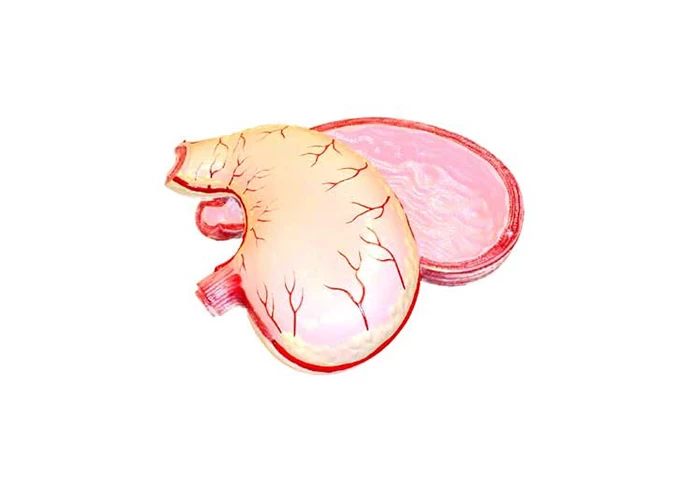

Մոդելը ծալովի է և ցույց է տալիս մարդու ստամոքսի անատոմիան՝ ստամոքսի մկանների կառուցվածքը, ստամոքսի պատի բոլոր շերտերը, լորձաթաղանթի ծալքերի ռելիեֆը, արյունատար անոթները և կերակրափողի ու ստամոքսի սփինտերի միացումը։ Այն պատրաստված է պլաստմասից և ներկված է վառ բնական գույներով։ Մոդելի չափսերն են առնվազն 25 x 20 x 10 սմ